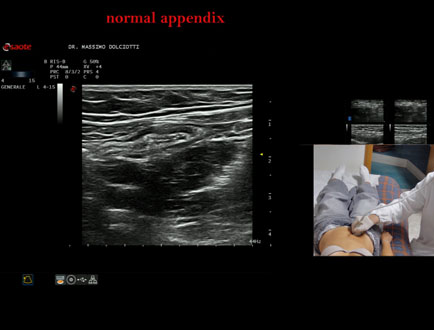

Data inserimento: 26/09/2025

Ecografia del: 12/09/2025

Strumento: Esaote MyLab Eight

Sonda: Lineare Multifrequenza 4-15 MHz

Età Paziente: F 24 anni

Motivazione dell'esame: da 3 mesi dolore al fianco destro.

Commento all'esame: le immagini ed il video documentano l'appendice di spessore normale (5,1-5,7 mm - v.n. < 6 mm).

Conclusioni: appendice normale (normal appendix).

Presentazione: Dr. Massimo Dolciotti - Ancona